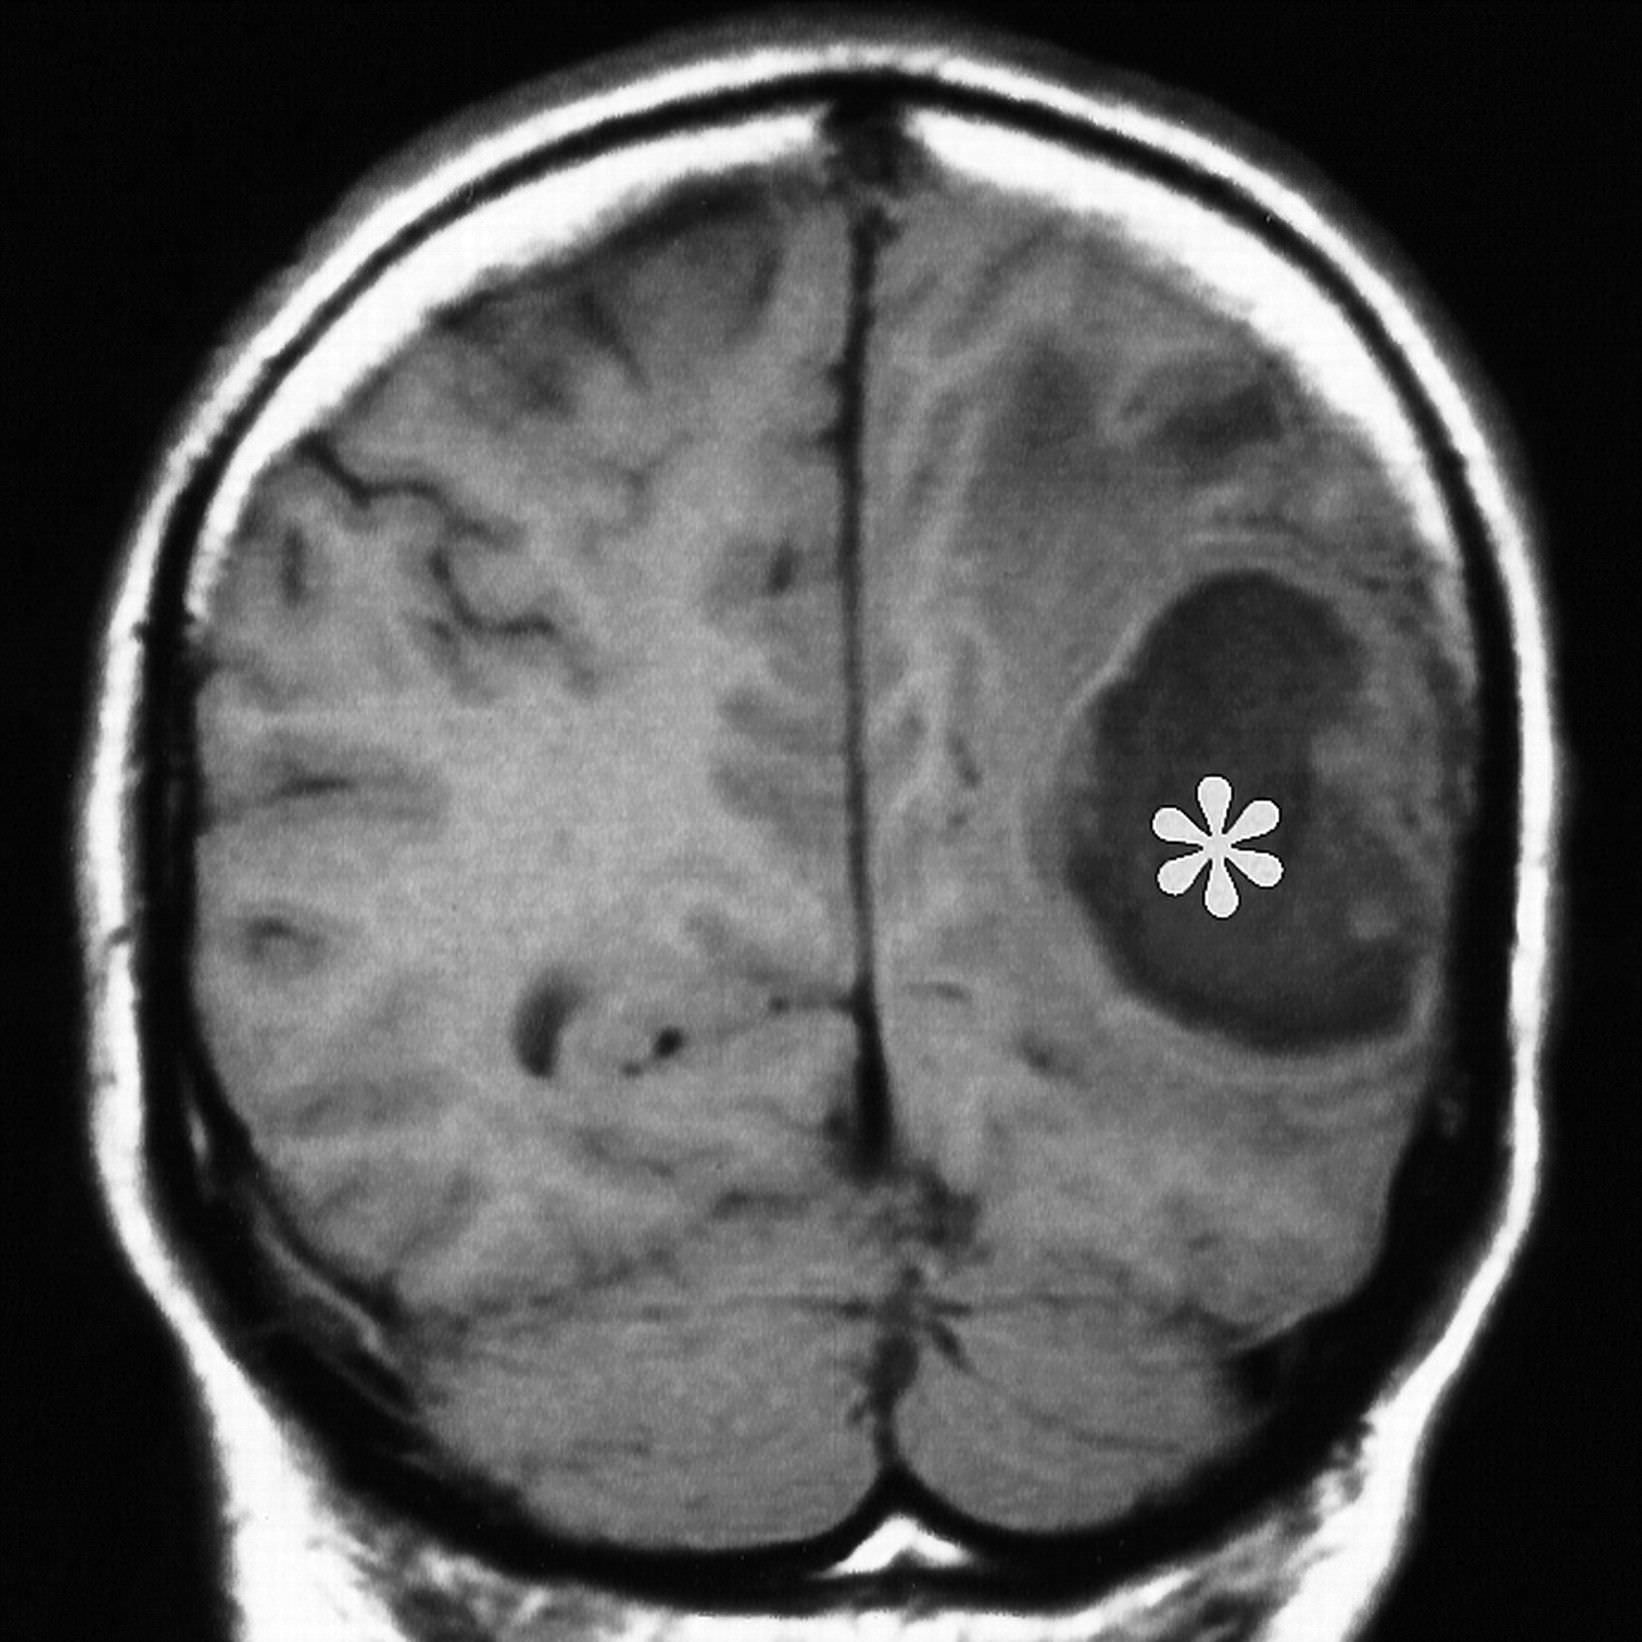

- 3 стадия (10-13 дней). Вокруг гнойной полости образуется защитная пленка, которая не дает образованию распространяться дальше.

- 4 стадия (3 неделя). Пленка полноценно уплотнилась. В некоторых случаях начинается регресс болезни или вокруг капсулы образовываются новые очаги заражения.

Дальше это только подготовка к хирургическому вмешательству. Врачи клиник на данный момент практикуют полное удаление абсцесса или его дренирование. Пунктуационная аспирация применяется на ранних стадиях или на этапе церебрита.

Её эффективность доказана в случаях, когда гнойник расположен глубоко в голове. Если неврология больного покажет наличие воздуха в абсцессе или ухудшение общего состояния пациента – новообразование нужно удалять.

Полное извлечение капсулы поможет предотвратить повторное заражение, но операцию нужно проводить осторожно, без нарушения целостности образования. Дальше антибиотики следует применять в течение 3 дней с постоянным наблюдением пациента